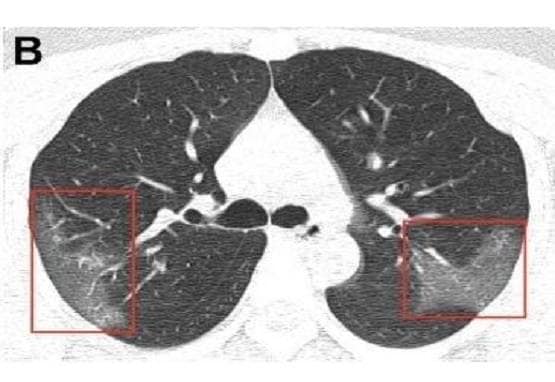

दरअसल, चीन के लंझाऊ स्थित एक अस्पताल में कोरोना वायरस संक्रमित 33 वर्षीय एक मरीज के सीने का X-Ray लिया गया. इसके बाद चौंकाने वाली तस्वीरें सामने आई. उन्होंने देखा कि सार्स की ही तरह कोरोना वायरस के भी लक्षण दिखाई दिए हैं. (Photo: Journal of Radiology)

जर्नल ऑफ रेडियोलॉजी के अनुसार डॉक्टरों द्वारा दिखाई गई  X-Ray रिपोर्ट में  फेफड़े के निचले हिस्से में कुछ दाग नजर आए. डॉक्टर्स ने इसे ground glass opacity बताया है.

(Photo: Journal of Radiology)

रेडियोलॉजिस्ट ने बताया कि जब उन धब्बों को ज़ूम कर देखा गया तो वे किसी शीशे के टुकड़ों की तरह नजर आए. ये साबित करते हैं कि वहां कुछ तरल पदार्थ इकठ्ठा हो गया है.